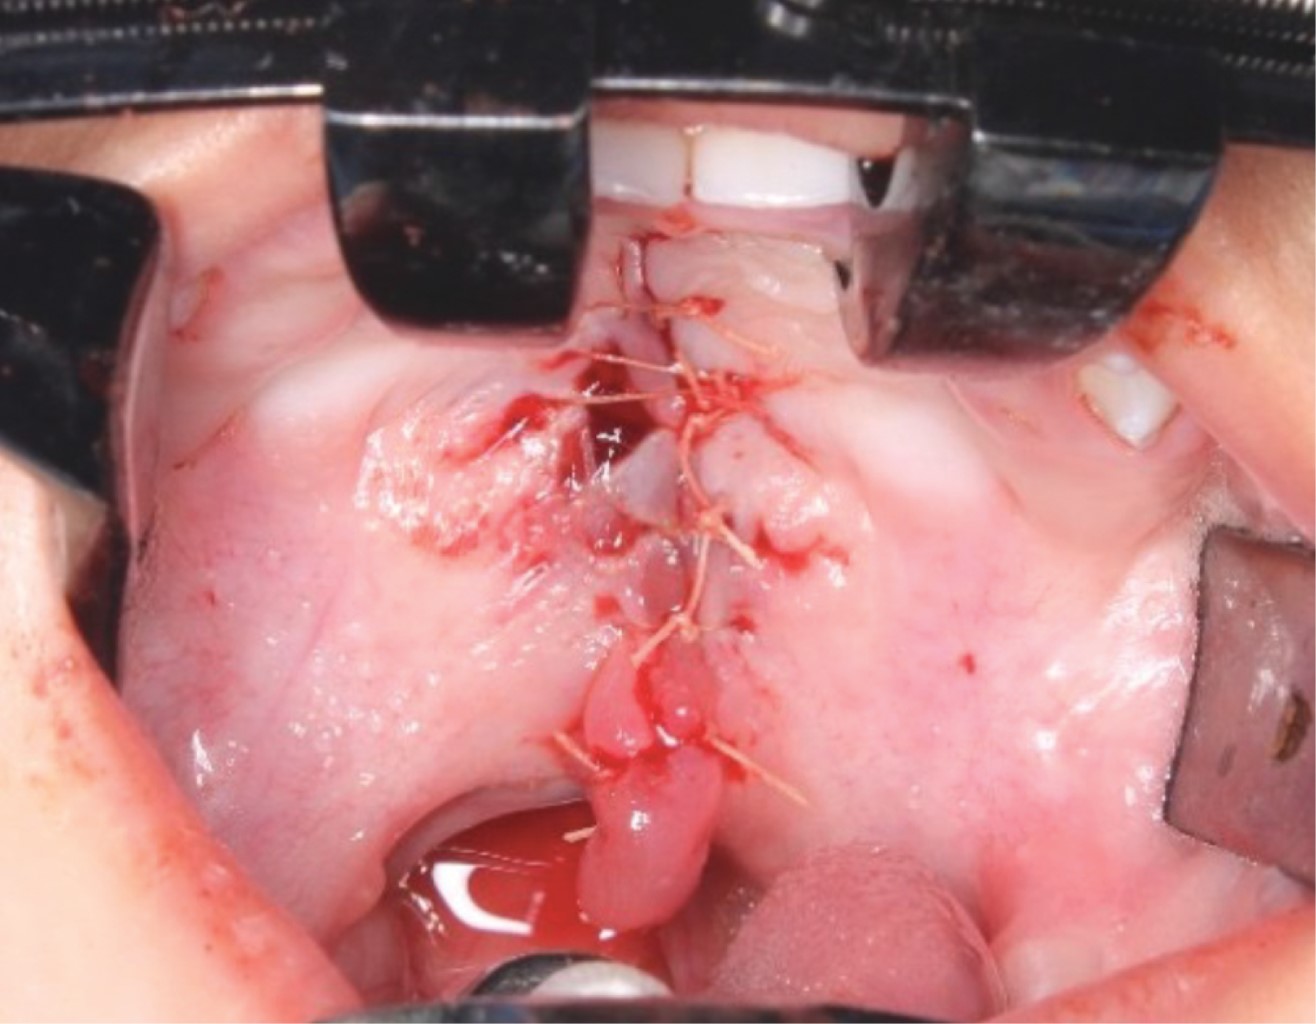

Se presenta el caso de un paciente pediátrico masculino, quien fue llevado al Servicio de Cirugía Maxilofacial del Centro de alta Especialidad "Dr. Rafael Lucio" a la edad de un año cinco meses. Fue valorado y diagnosticado con fisura de paladar secundario clasificación II de Veau (Figura 1), por lo que se le realizó palatoplastia mediante técnica de veloplastia intravelar bajo anestesia general balanceada; la cirugía se llevó a cabo sin complicaciones ni eventualidades (Figura 2). El paciente fue dado de alta; acudió a controles posquirúrgicos a la semana, al mes y a los seis meses; durante este seguimiento fue posible observar la presencia de una fístula palatina Pittsburgh IV +, Cohen II, la cual provocaba paso de líquidos desde la cavidad oral a la nasal (Figura 3).

Figura 2